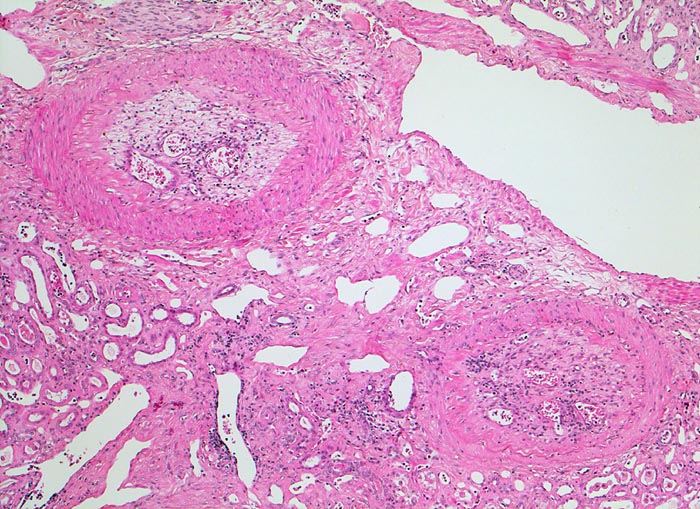

PathoPic – image database / PathoPic ID 4866 - alter rekanalisierter Gefässverschluss

alter rekanalisierter Gefässverschluss

Diese intrarenalen Arterienäste weisen alte organisierte und durch kapilläre Gefässe rekanalisierte embolische Verschlüsse auf.

Die meisten Arterienverschlüsse in der Niere sind embolisch bedingt. Die Niere ist wegen ihrer starken Durchblutung oft von Embolien betroffen. Da die Niere durch Endarterien versorgt wird, handelt es sich um anämische Infarkte. Thrombotische Verschlüsse bei fortgeschrittener Atherosklerose (Diabetes mellitus) oder im Rahmen einer Vaskulitis sind selten.